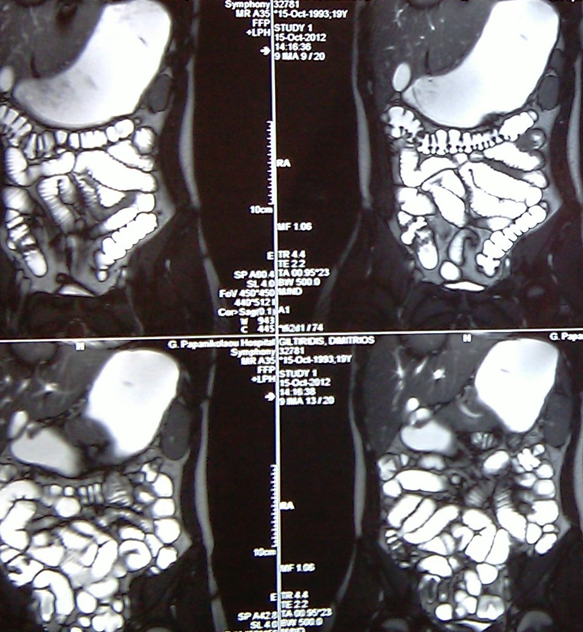

Mesenteric root infiltration — Absolute contraindication for cytoreductive surgery (Courtesy Dr. V. Penopoulos)